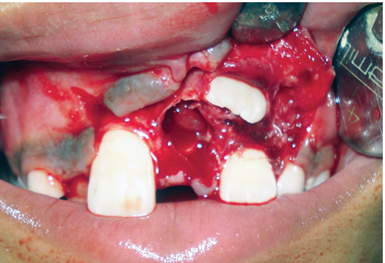

Việc kiểm soát tình trạng răng mọc chậm do răng thừa có thể được thực hiện bằng hai phương pháp. Thứ nhất, bằng cách điều trị bảo tồn, chỉ bằng cách phẫu thuật loại bỏ răng thừa (hình 4). Thứ hai, bằng cách phẫu thuật loại bỏ răng thừa kết hợp cùng lúc với chỉnh nha kéo răng cửa ngầm lên (hình 5).

image 20231218155055 15 533x390 image 20231218155055 16 514x374 image 20231218155055 17 482x336

R21 chưa mọc, R11 đã mọc (a), Răng thừa (b), R22 (c) (b)Răng thừa thứ nhất, (a) răng thừa thứ 2, (c) R21 ngầm chưa mọc Phẫu thuật lật vạt:(a) răng thừa thứ 1, (b) R21 ngầm, (c) R22

image 20231218155055 19 502x340

Răng thừa thứ 1đã được nhổ Bộc lộ răng thừa thứ 2 Hình ảnh 2 răng thừa

Hình ảnh sau phẫu thuật 6 tháng, R21 đã mọc lên sau khi loại bỏ 2 răng thừa

Hình 4: Minh họa cho phẫu thuật lấy răng thừa đơn thuần ở một bé trai 9 tuổi